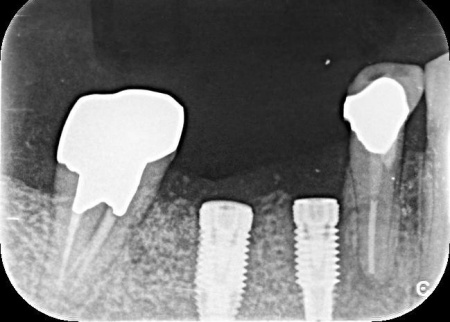

次にCT検査を行い、骨の量や神経の位置を確認したうえでインプラント治療の計画を立てています。

完成した治療計画をもとに、インプラントをあごの骨に埋める手術を実施しました。

一定期間をおいてインプラントがあごの骨に定着したことを確認したあと、歯ぐきの上にインプラントの一部を出すための二次手術を行いました。

歯ぐきの治癒を待ってから型取りを行い、インプラントの上に装着する人工歯を作製・装着して治療を終了しています。